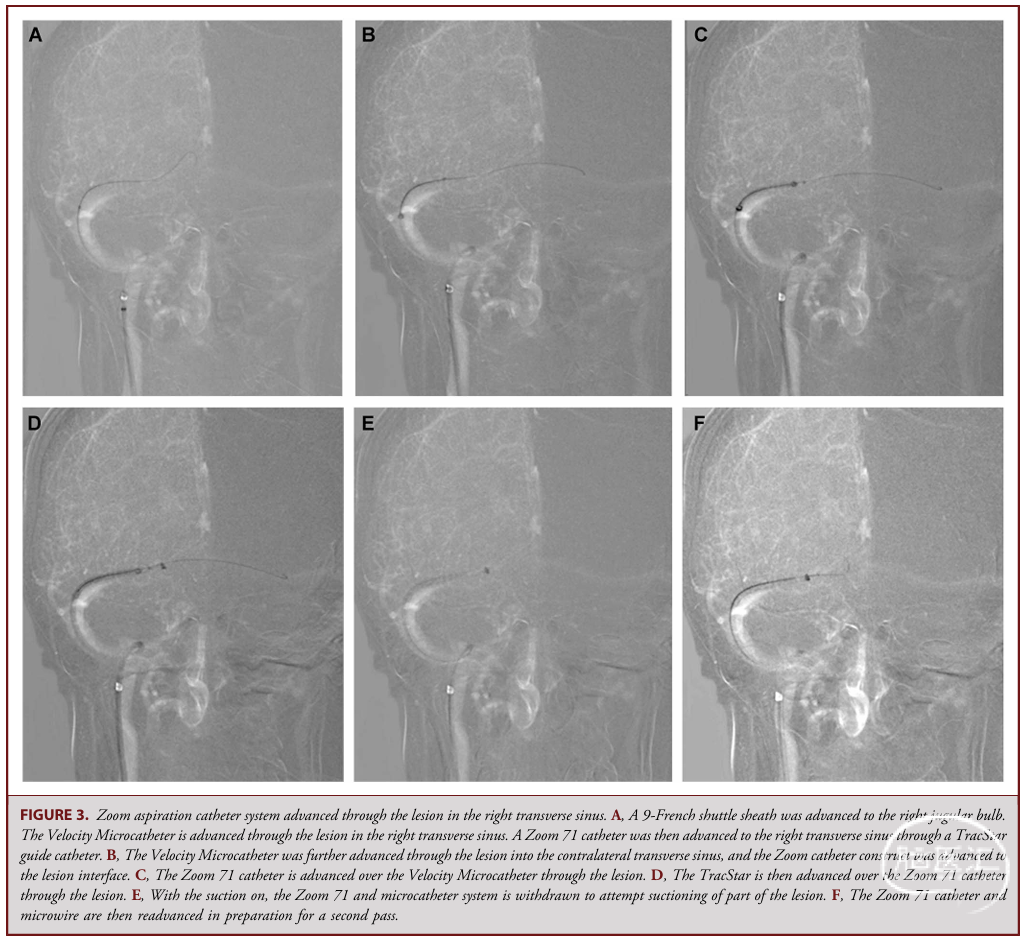

(1)经股静脉入路,将导引导管置于颈静脉球水平,微导管+抽吸导管送至病变界面。

(2)启动真空泵抽吸,经Telfa敷料垫过滤抽吸物,判断是否有诊断价值(本例无)。

(3)经微导管输送Solitaire X支架取栓器,穿越病变后缓慢回撤,利用支架剪切力捕获组织。

(4)术后即刻行血管造影+锥形束CT,确认无血管损伤、对比剂外渗。